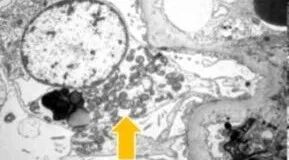

结合肾穿刺标本的电镜复核,发现足细胞及肾小管上皮细胞内可见少量形态异常的线粒体,最终明确诊断为CoQ8B肾病。

CoQ8B肾病是一种与线粒体功能障碍相关的遗传性肾病,可表现为蛋白尿、FSGS样病理改变及肾功能进行性下降,且并非仅发生于儿童,成人同样可能发病。